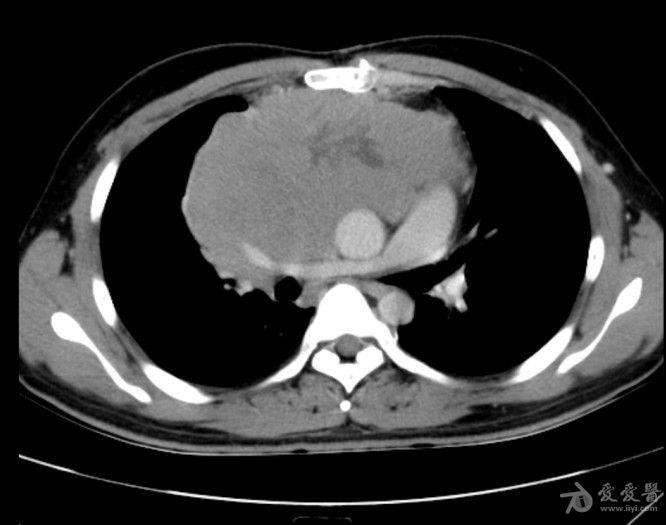

病例19恶性胸腺瘤

图片尺寸657x507

增强后呈厚壁环形强化,大小约60×38mm,胸腺来源低度恶性肿瘤可能.